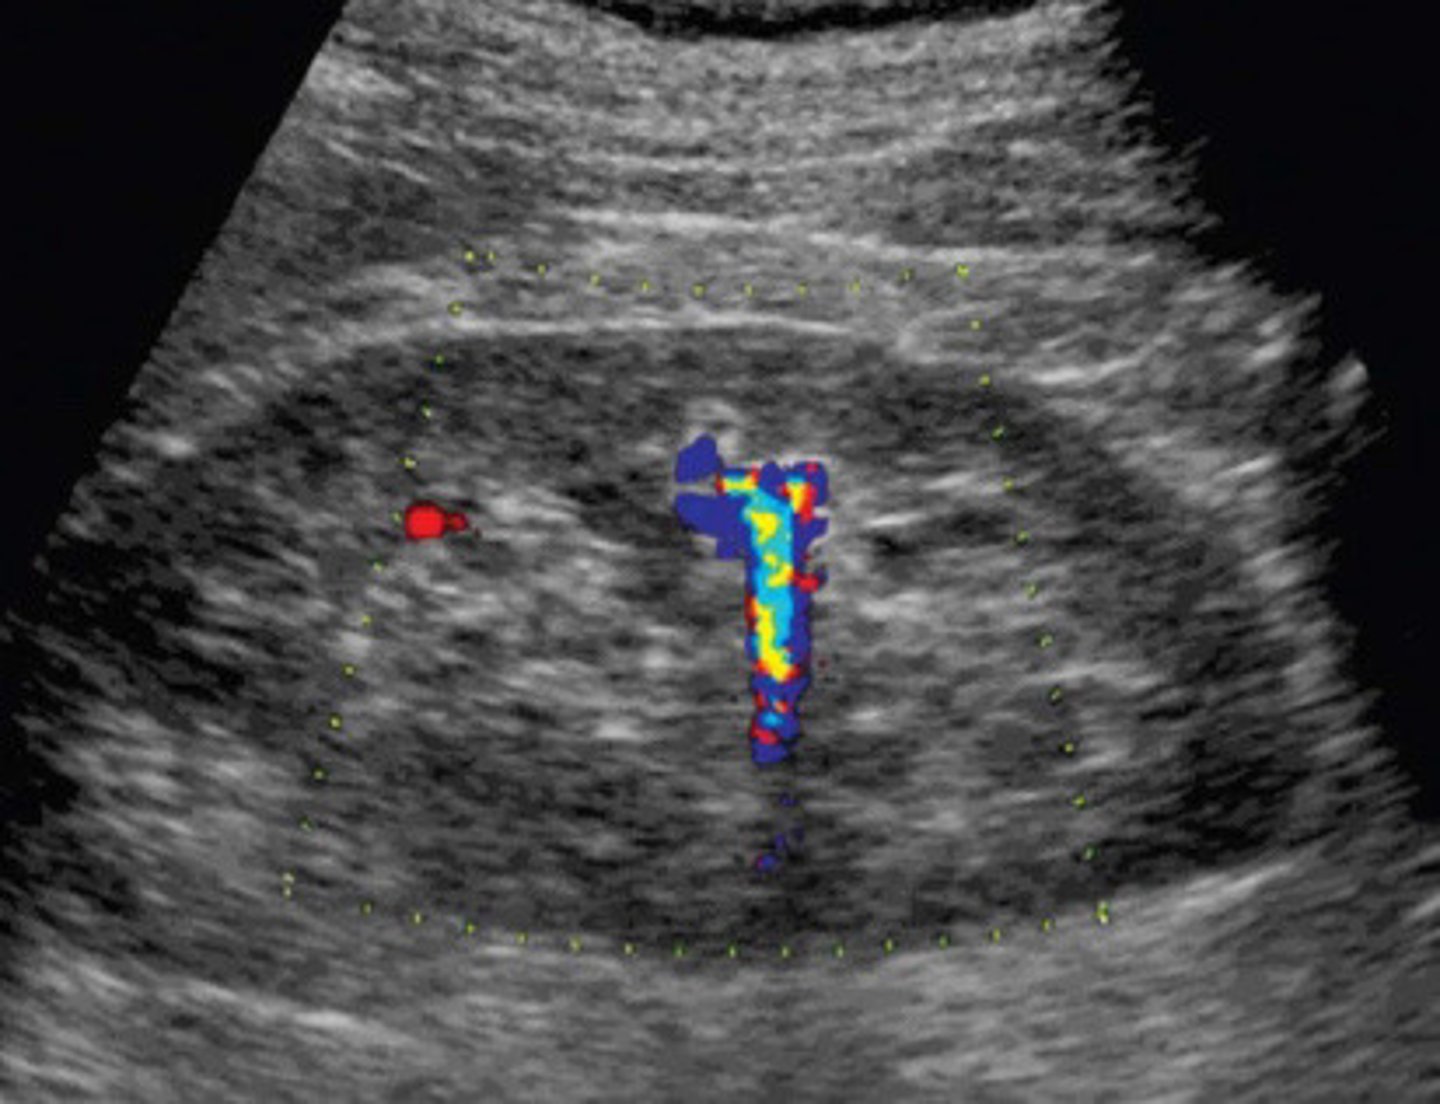

Stone now identified with the twinkle artifact

What does this image show

Colour reverberation

What is the twinkling artifact

Colour or power Doppler

What mode do you have to use in order to be able to see the twinkling artifact

Twinkle artifact from staghorn calculi